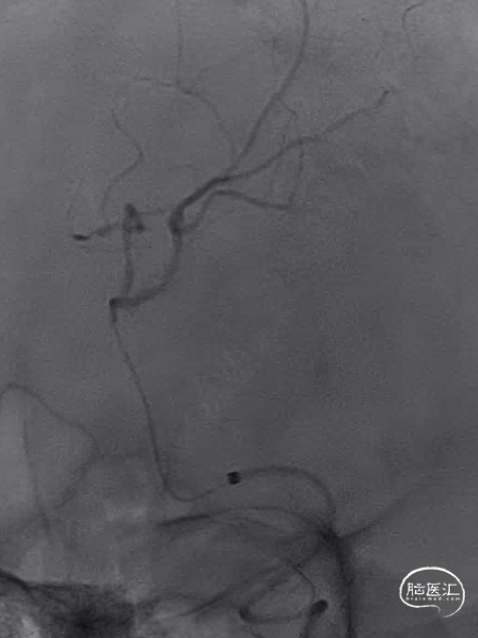

DSA:

取栓后即刻造影。

15min后复查造影,明显回缩。